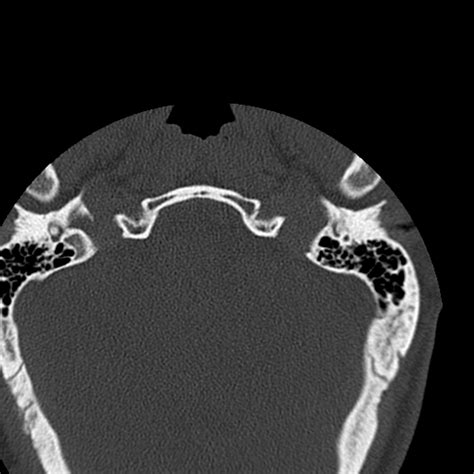

• Computed Tomography (CT) Scan: This is the gold standard for diagnosing occipital condyle fractures. CT scans provide detailed images of the bony structures and can help identify the location and extent of the fracture.

Occipital condyle fractures are classified based on their pattern and mechanism of injury. The most commonly used classification system is the Anderson and Montesano classification, which categorizes these fractures into three types:

Type II Basilar skull fracture extending into the occipital condyle Lateral mass displacement